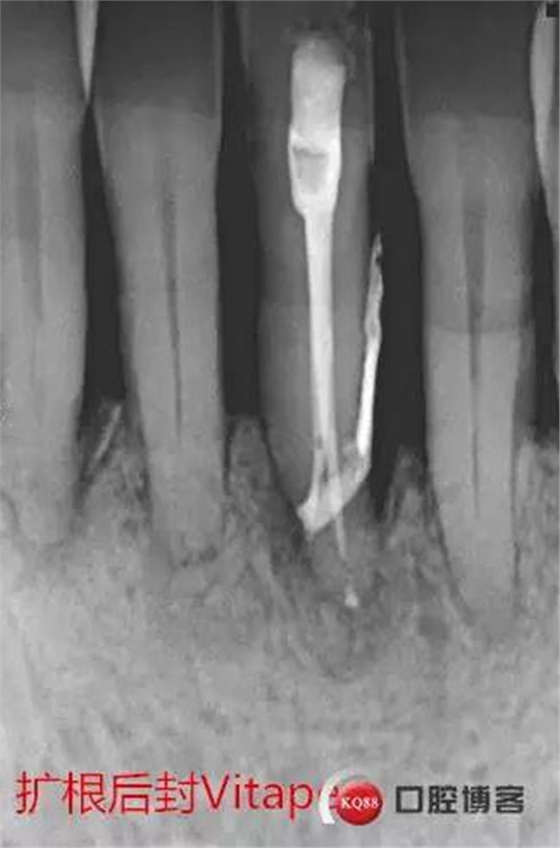

處理:31去暫封,手用銼疏通根管,沖洗,機(jī)擴(kuò)至04錐度30#,超聲蕩洗,封維塔,拍片。

由于兩次根管內(nèi)封藥后,頰根處均有多余藥物擠出根尖孔,考慮根尖孔處受破壞或根尖周炎癥導(dǎo)致牙周膜疏松,故封藥兩周后復(fù)診。